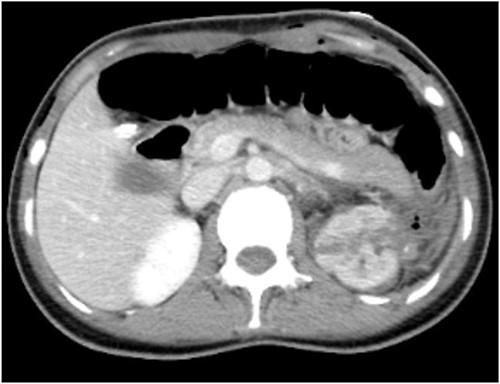

To further clarify the diagnosis, an intensive computed tomography (CT) examination of the abdominopelvic region was performed, revealing a soft tissue mass and renal tumor in the left kidney, multiple small cysts in both kidneys, and multiple high-density foci in the pelvis, lumbosacral vertebral body, and adnexa (Fig. 1).

CT shows uneven density and disordered structure in the upper pole of the left kidney, with turbidity and increased density in the surrounding fat spaces.